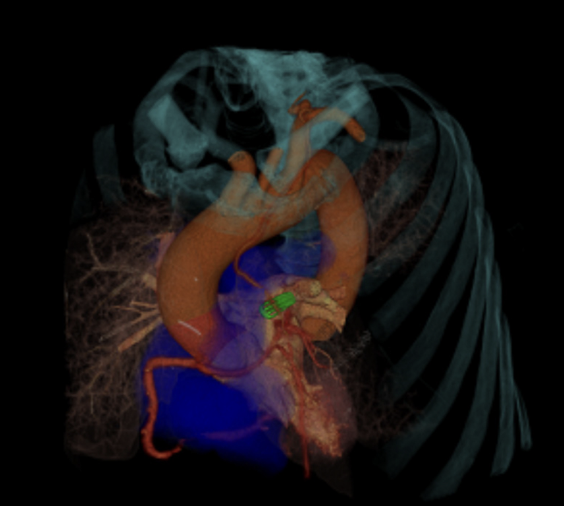

🫀✨ Cover-worthy cardiology ✨🫀 🍬This wasn’t just eye candy—it was last year’s journal cover. A stunning fusion of anatomy, pathology, and advanced cardiac imaging, submitted by one of our own cardiologists, Alex Rodriguez MD FACC! When clinical insight meets next-level

Just a reminder that cardiac imaging can be both 🧠 clinically brilliant 🎨 visually unreal This image was one of the @journalCCT covers last year—submitted by one of our cardiologists, Alex Rodriguez MD FACC🫀📸 #Radtwitter #Cardiology #Radiology #Radres